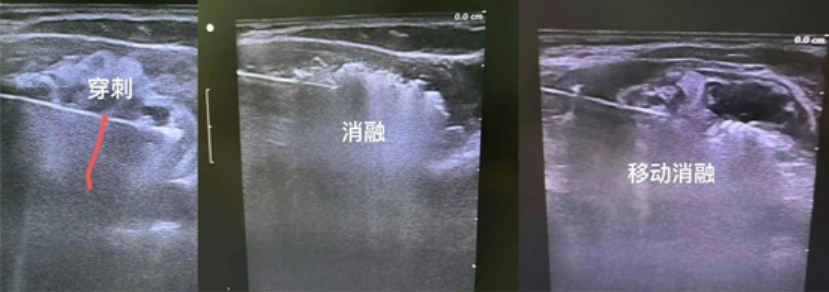

整個治療在超聲的引導(dǎo)下進(jìn)行。B超掃描定位,首先以左側(cè)甲狀腺腫物為靶區(qū),B超引導(dǎo)下,用細(xì)針行穿刺活檢,送術(shù)中快速病理檢查,結(jié)果提示為未見癌細(xì)胞。因腫物巨大,術(shù)中還在甲狀腺與氣管間隙、與左側(cè)頸總動脈間隙、與食管間隙,注射生理鹽水進(jìn)行水隔離處理,增大治療組織與周圍組織的間隙,保護(hù)周邊氣管、食管、頸部大血管、喉返神經(jīng)、喉上神經(jīng)等重要組織結(jié)構(gòu)。

隨后,以30W的功率開始微波消融。按由下至上,由內(nèi)至處,由深至淺的順序動態(tài)調(diào)整數(shù)微波刀位置,直至消融范圍覆蓋靶區(qū),拔除微波刀。就這樣,梅麗的甲狀腺結(jié)節(jié)被逐步“瓦解”。

微波消融巨大甲狀腺腫物